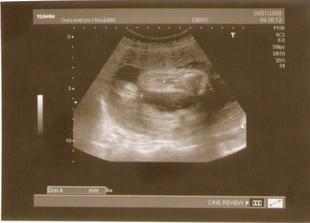

22.8.2007 - 2. ultrazvuk, miminko má 51 mm

19.9.2007 - 3. ultrazvuk, miminko má už 15,8 cm 🙂, odběry na tripple test, váha 61 kg

30.10.2007 - ultrazvuk v Gennetu, maličká je v pořádku a menší jen o týden

6.12.2007 - jedu na 3D ultrazvuk

9.1.2008 - ultrazvuk, beruška na nás plazila jazyk, mrkala a polykala plodovou vodu 🙂 už je připravená hlavičkou dolů, váha 68 kg